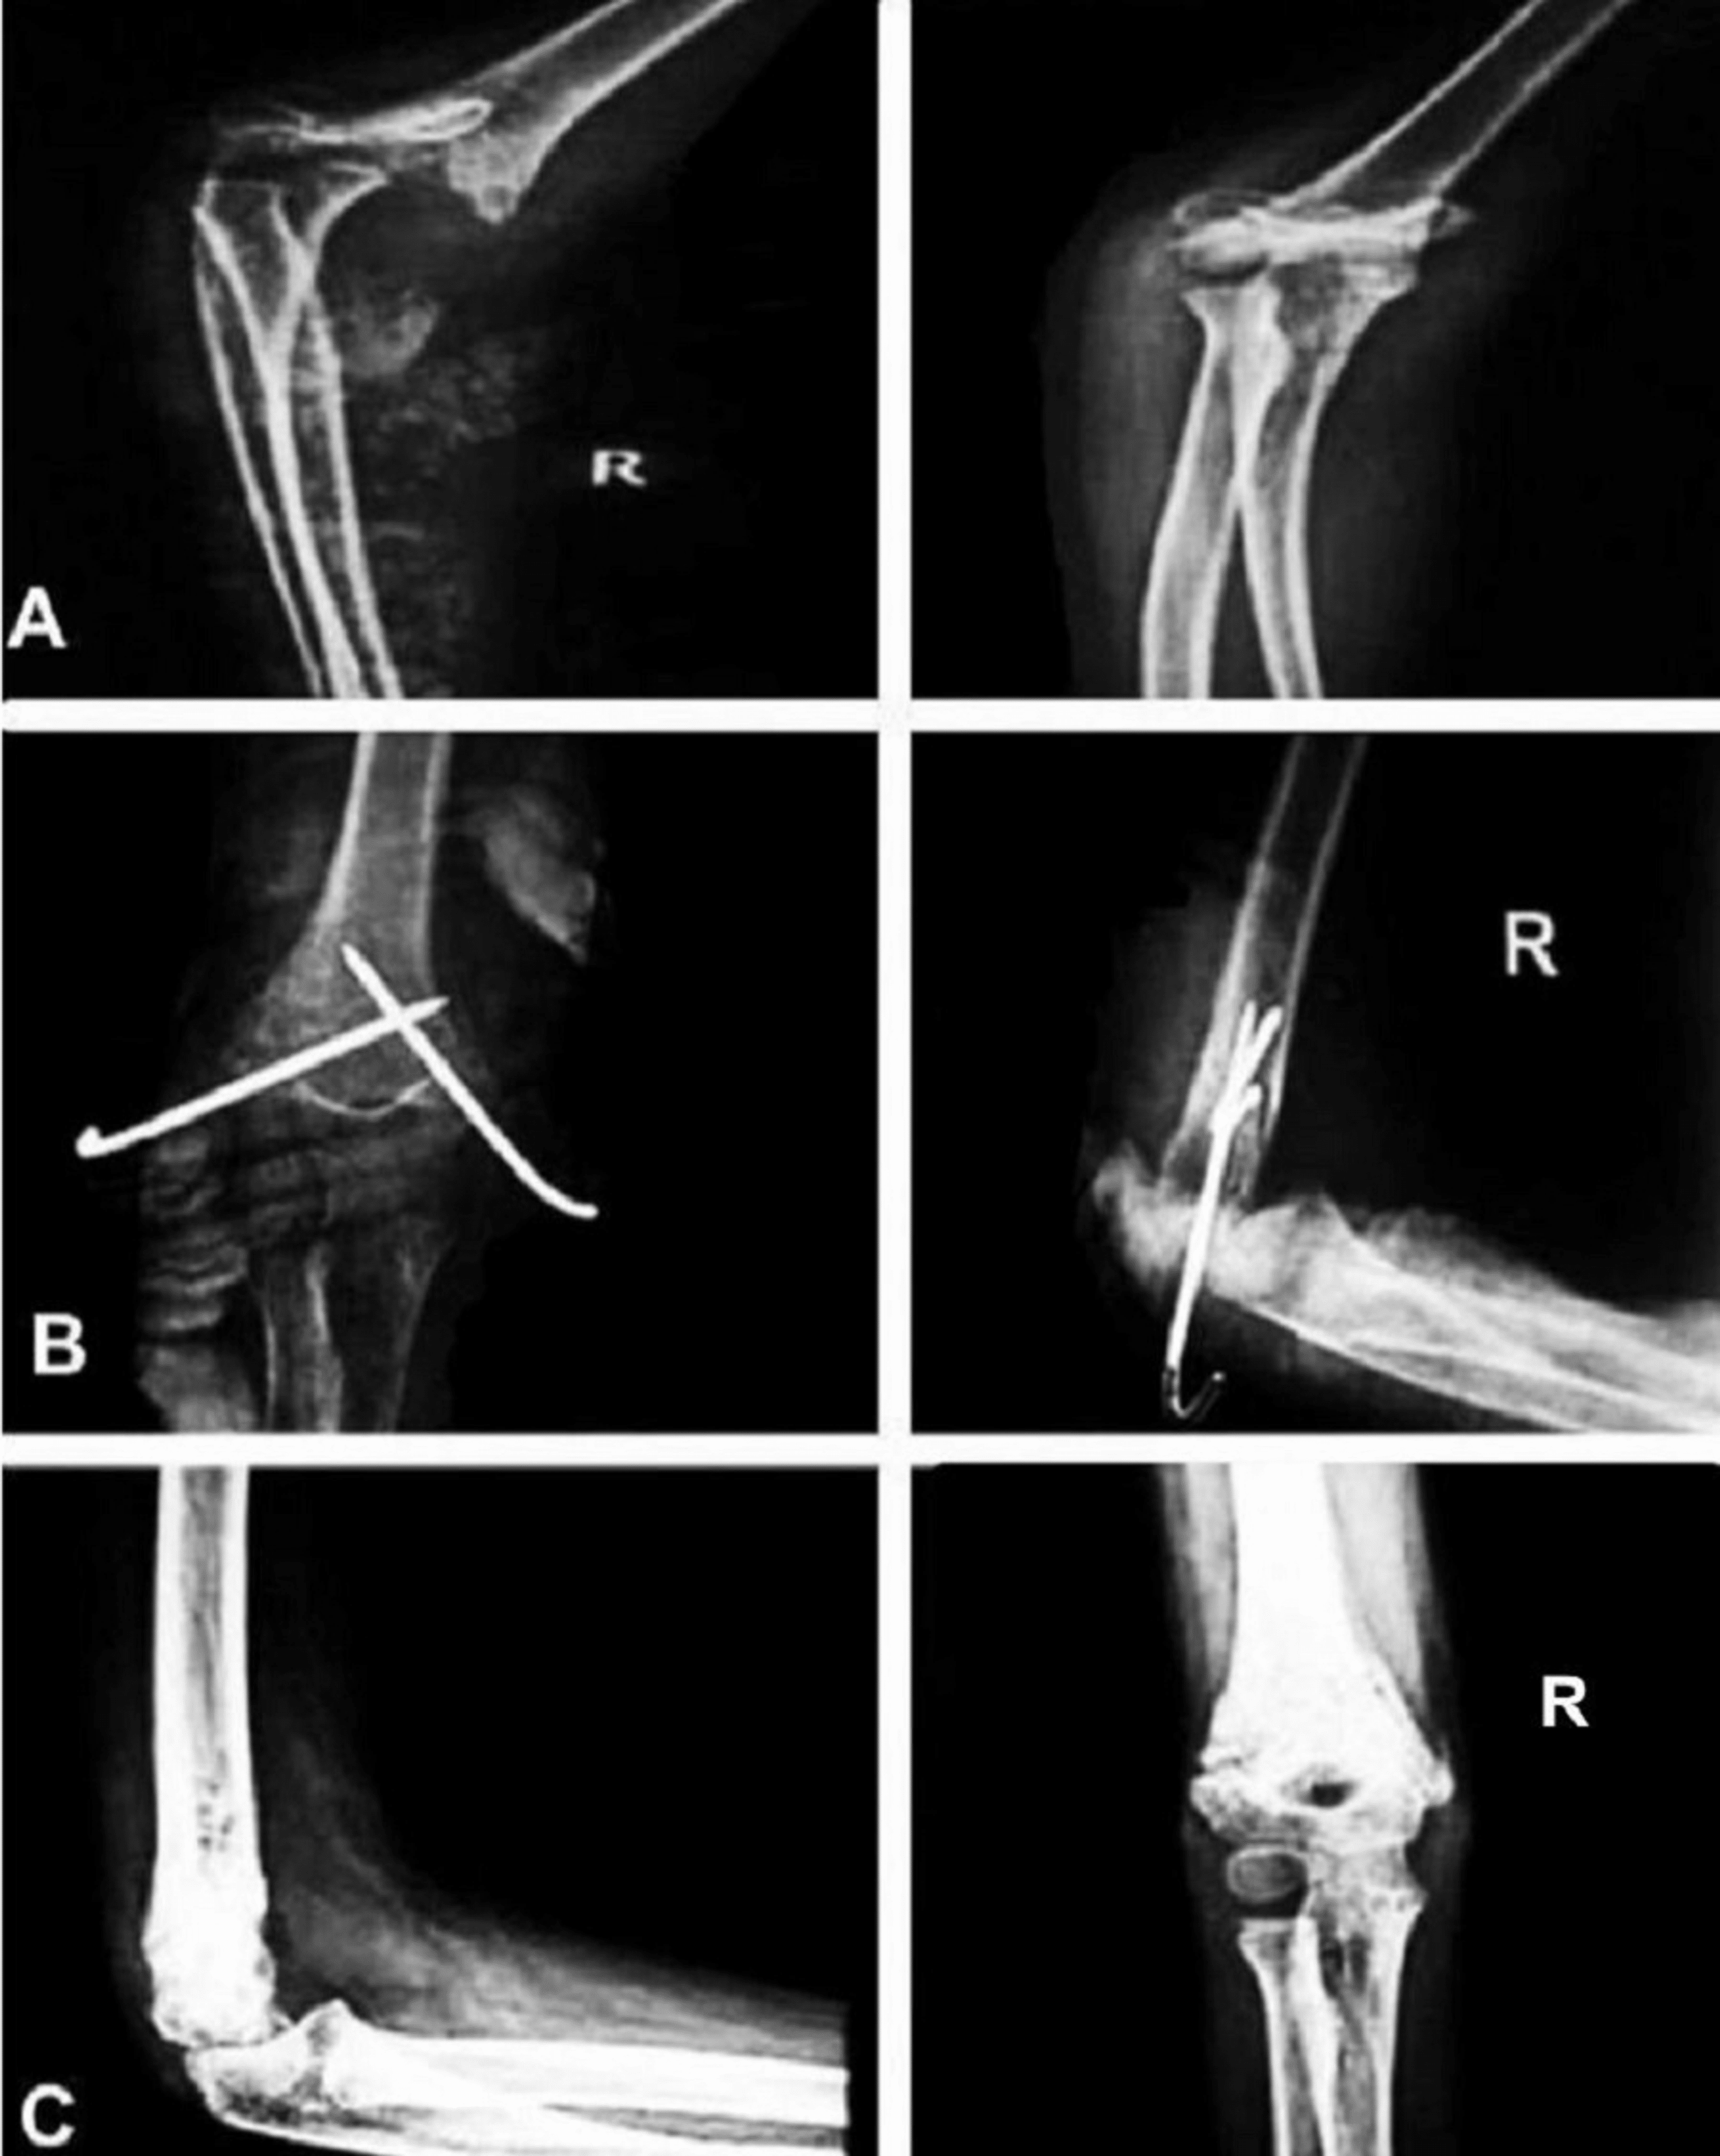

supracondylar fracture pre (A) and post (B) managed with open reduction Collar And Cuff For Supracondylar Fracture Your child’s arm will be placed into a temporary plaster cast, supported by a collar and cuff. Swelling and bruising at the fracture site is normal. Application of a high collar and cuff uses the triceps to reduced posterior angulation of the fracture. Detailed step by step desription of collar and cuff immobilization for simple metaphyseal, incomplete, displaced located in. Collar And Cuff For Supracondylar Fracture.